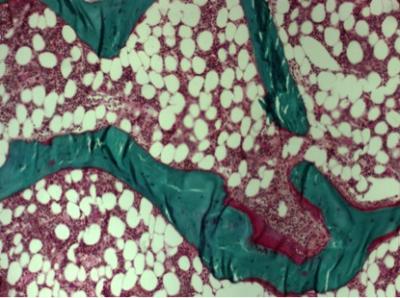

Bone samples were investigated using bone histomorphometry, a microscopic method that provides information about bone metabolism and remodelling. In children with vertebral fractures, there were changes in bone composition, such as lower carbonate-to-phosphate-ratio and increased collagen maturity, which could explain the increased fracture risk. The results also suggest that in children who have undergone kidney, liver or heart transplantation, the various changes related to bone microarchitecture and turnover may be more important predictors of fracture risk than lowered bone mineral density alone. Early detection of such changes in bone quality could help prevent fractures.

Osteoporosis is the most common metabolic bone disease characterized by abnormal bone formation and resorption which lead to increased risk of bone fractures. However, the present diagnostics based on the measurement of bone mineral density predict fractures only moderately. In addition to decreased bone mineral density, changes in bone quality could explain increased fragility related to osteoporosis. The present study confirmed that bone histomorphometry is needed in clinical practice to study remodelling balance in bone in certain patient groups.

The histomorphometry laboratory at the University of Eastern Finland in Kuopio is one of the few in the world analyzing clinical bone biopsies. More than 70 patient samples are analyzed annually. Over 30 years of expertise in quantitative histomorphometry have formed a solid basis for high quality research. Recent projects focus on paediatric patients with osteoporosis, genetic disorders and insufficiency fractures.

In the bone quality research programme, bone material characteristics are assessed by established methods, such as quantitative bone histomorphometry, microCT and mechanical testing, as well as by newly developed methods, such as nanoCT, IR/Raman spectroscopy, nanoindentation and acoustic microscopy. The quantitative techniques provide information on factors affecting bone's fracture resistance, not hitherto possible.